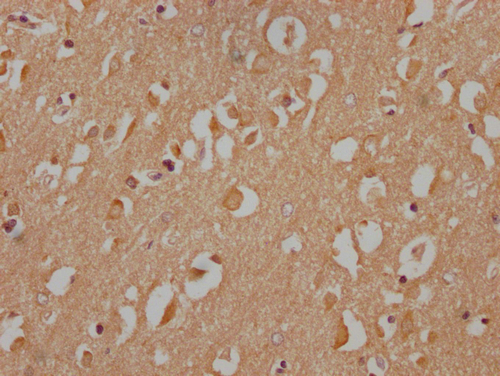

IHC image of CSB-PA890690NA172nphHU diluted at 1:100 and staining in paraffin-embedded human brain tissue performed on a Leica BondTM system. After dewaxing and hydration, antigen retrieval was mediated by high pressure in a citrate buffer (pH 6.0). Section was blocked with 10% normal goat serum 30min at RT. Then primary antibody (1% BSA) was incubated at 4°C overnight. The primary is detected by a Goat anti-rabbit IgG labeled by HRP and visualized using 0.05% DAB.